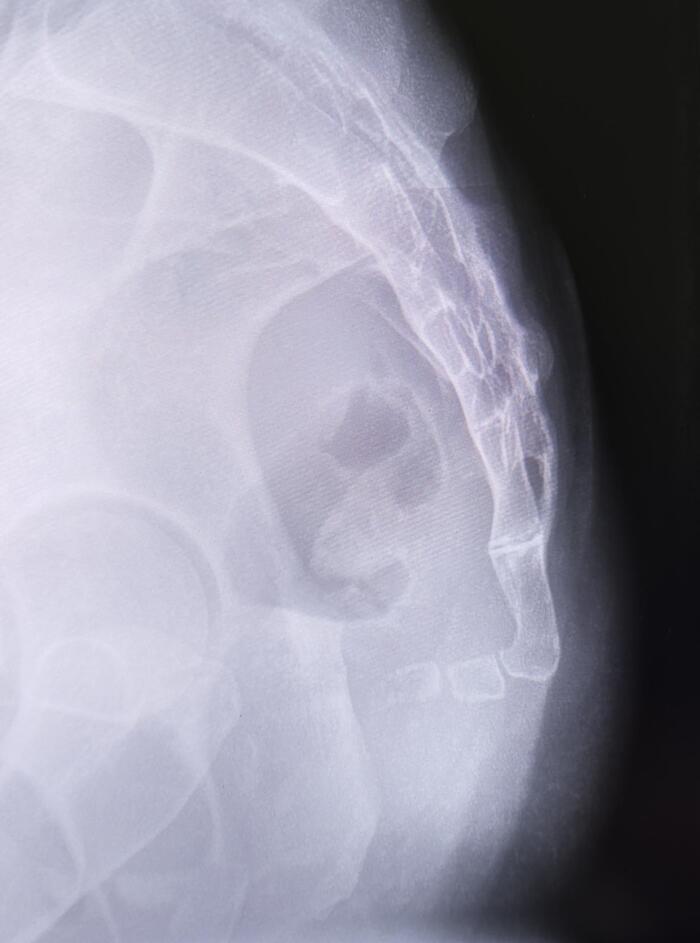

Рентген крестца и копчика в боковой проекции пациентки 30 лет., жалобы на боли в копчике при длительном положении сидя, травму в анамнезе отрицает.

Травматических, деструктивных изменений крестца и копчика не выявлено. Костная структура не изменена. Крестцово-копчиковый угол-90 градусов(норма-150 ± 3,7 градусов).

Заключение: Антеверзия копчика.

Копчик сильно загнут вперед, что является наиболее частой причиной кокцигодинии (боли в копчике).